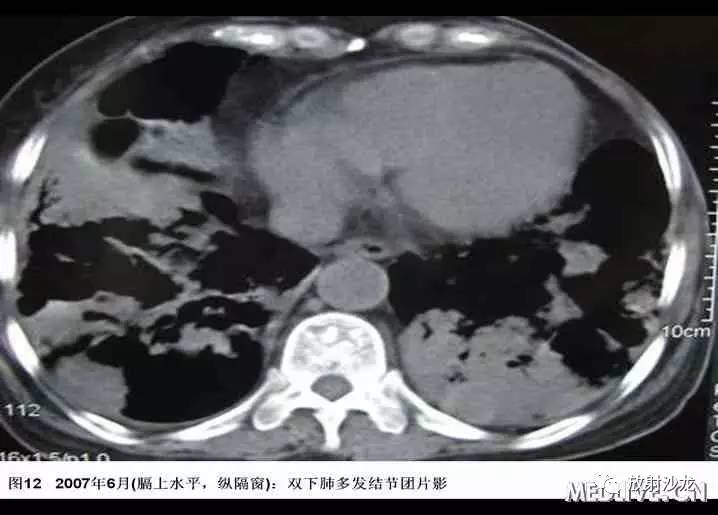

患者于2006年4月初无诱因出现间断咳嗽,少量黄痰,无咯血、胸闷、胸痛。2006年4月中下旬出现发热,最高体温38℃,当地血常规:WBC:6.7G/L,GR:78%,胸片示“右下肺纹理增粗,局部可见斑片索条影,右侧肋膈角钝”;考虑“肺部感染”,予拜复乐(莫西沙星)、罗氏芬(头孢曲松)治疗3天后体温降至正常,但仍有间断咳嗽、咯痰,遂于2006年5月中旬就诊某一上级医院,胸部CT“右下肺及胸膜下可见多发结节、斑片影,局部可见支气管扩张”(见图1-4),行胸腔镜肺活检,病理经多家医院综合会诊后考虑“淋巴组织增生性病变,但是诊断淋巴瘤证据不足”,未予特殊治疗。

入院后患者最高体温在38℃左右,给予“拜复乐及大扶康”治疗后无显效,复查胸部CT提示肺内病变较2007年3月有加重(见图9-12),遂再次行CT引导下经皮肺穿。穿刺后患者最高体温维持在39℃左右,考虑感染不能完全除外,于2007年6月19日起加用稳可信0.5g Q8h及复达欣1.0g Q8h,6月21日加用口服大扶康200mg Qd,发热未见改善。结合两次肺穿及外院VATS的标本,病理科诊断“肺Castleman病(多中心型)(见图13)” 免疫组化:CD3(+)、CD20(+),AE1/AE3(+),CD21(+)”。6月21日转入血液科化疗,并于6月22日予CHOP方案化疗(CTX 600mg d1, 400mg d4, 西艾克4mg d1, 艾达生80mg d4, 强的松80mg d1-5)。化疗后未再发热,咳嗽、咳痰症状缓解,6月27日复查CXR示右下肺团块影较1月前吸收予以一疗程CHOP化疗后,患者体温正常,复查胸片提示右下肺阴影较前有明显吸收。后又间断予以CHOP方案化疗3程,2008年2月初,因受凉后发热,出现渐加重的气短,家属及患者放弃进一步诊疗,于2008年2月下旬去世。